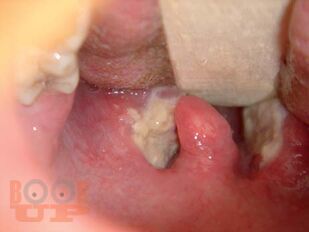

В основу монографии положены результаты собственных наблюдений и исследований авторов, касающиеся более 3500 больных с различными клиническими формами дифтерии. Клиника заболевания представлена в сопоставлении со сходными с нею другими инфекционными болезнями. Большое внимание уделено совершенно новым аспектам патогенеза дифтерии и особенностям ее течения в современных условиях, факторам риска неблагоприятного течения инфекционного процесса, причинам летального исхода болезни, а также разработанной и опробованной авторами на практике методике организации эффективного лечения больных в период нахождения их на догоспитальном и госпиталь ном этапах, включающей оказание неотложной помощи и ведение интенсивной терапии.